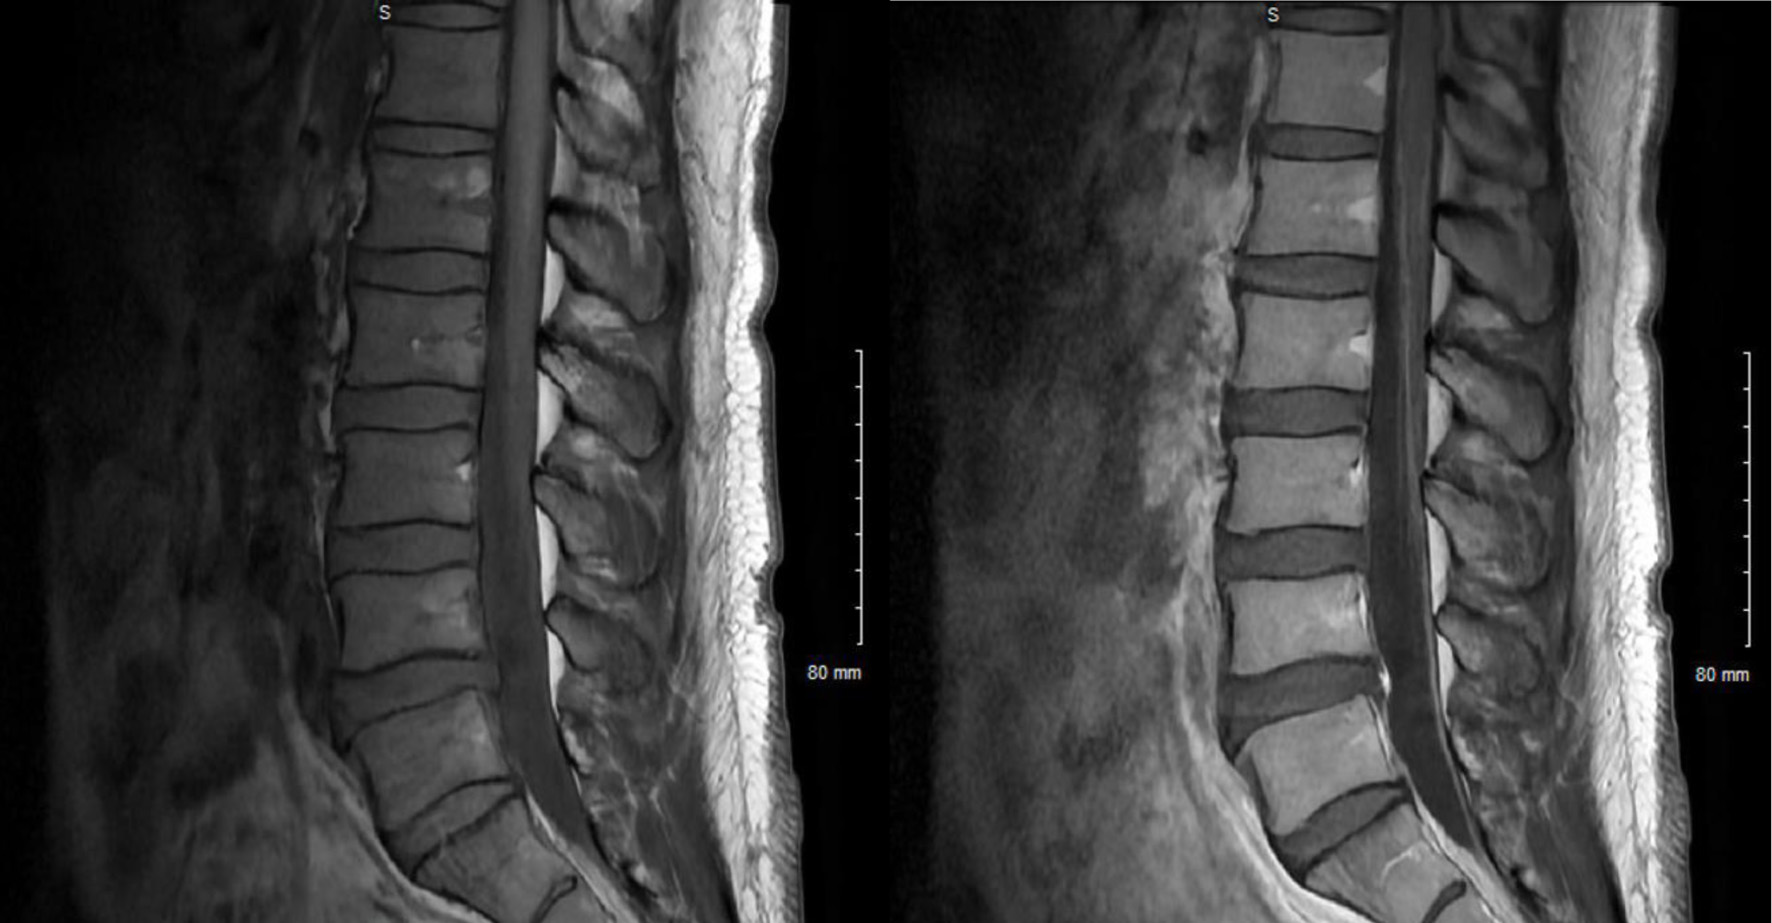

Labs are listed in Table 1. Serum VZV was not tested but vesicle scraping from his lesions was positive for VZV. He underwent MRI of his cervical, thoracic, and lumbar spine which showed enhancing nerve roots in the cauda equina (Fig. 2). Lumbar puncture was recommended to patient; however, he refused. IV acyclovir was administered for 14 days, after which the regimen was converted to oral valacyclovir. He was also started on cART. He has not been seen for follow-up.

Figure 2. Pre-contrast T1-weighted sagittal images of the L-spine (left) and post-contrast (right) with enhancement of cauda equina nerve roots.

In contrast to the first case, the second case demonstrates a distinctly different presentation of VZV-associated radiculitis. This patient exhibited active VZV skin lesions along with unilateral lower-leg symptoms. Because his involvement was limited to radiculitis—supported by MRI findings showing enhancement of the cauda equina roots—his examination was notable for hyporeflexia. As a result, the discussion about potential treatment is different. While the data are limited in this setting, one article recommended treating VZV radiculitis without obvious meningitis in immunocompetent hosts with only oral acyclovir [19]. One prospective observational cohort study of the Danish Group of Infections of the Brain database showed that in VZV meningitis regardless of immunocompetence early administration of antiviral treatment was not associated with improved outcomes 30 days after discharge [20]. Steroids were generally not indicated.